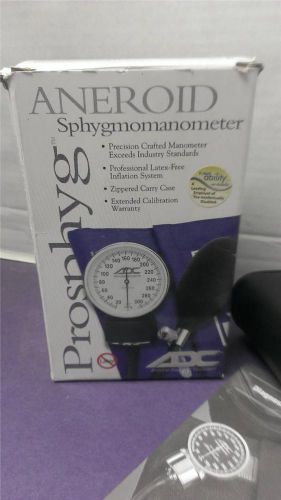

DIAGNOSTIX Adult Large Black Sphygmomanometer-Latex Free (B4)